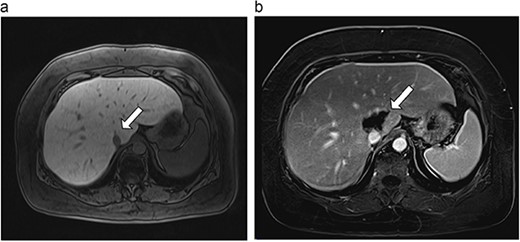

Six patients with six primary or secondary tumors of the caudate lobe were identified (Table 1). Median age at diagnosis was 68 years (51–77 years); two patients were female. Primary disease process was colon adenocarcinoma (n = 4; Figs 3–6), hepatocellular carcinoma (HCC; n = 1; Fig. 7) and metastatic pancreatic neuroendocrine tumor (n = 1; Fig. 8). All patients with colon adenocarcinoma received systemic therapy with 5-fluorouracil, oxaliplatin, and leucovorin (FOLFOX) prior to microwave ablation of hepatic metastases. The patient with metastatic neuroendocrine tumor had progression of hepatic metastases on lanreotide prior to microwave ablation. The patient with HCC had previously been treated with transarterial embolization and cryoablation of tumors, but had recurrence of disease, which was managed with microwave ablation.

| 1 (3a,b) | 61, F | Colon adenocarcinoma | 6-month FOLFOX | 1 | Laparoscopic microwave ablation | 6 | 40.4 | 34.4 | 10 | No |

(a) Pre-ablation MRI demonstrates 6 mm lesion in caudate lobe of liver. (b) Post-ablation MRI (18 days postoperatively) demonstrates 40.4 mm complete ablation site in caudate lobe of liver.